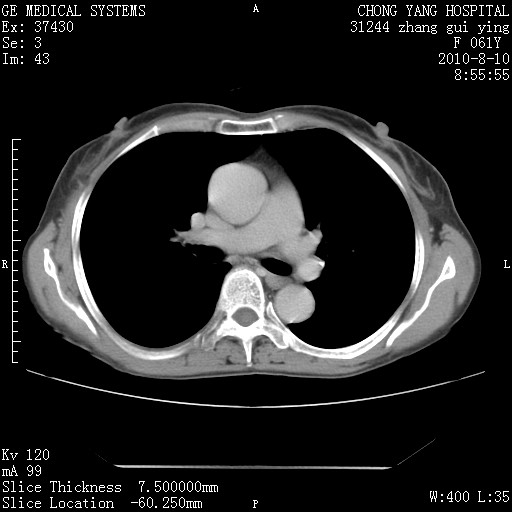

标题: CT28314:F61Y胸部增强,发热咳嗽一周入院,后面的为一周前平 [打印本页]

标题: CT28314:F61Y胸部增强,发热咳嗽一周入院,后面的为一周前平

1、支持考虑右侧中央型肺癌伴右肺中叶节段性不张及下叶支气管黏液痰栓    2、左肺上叶舌段感染。

支持3楼意见,还要考虑:纵隔及肺门淋巴结转移、右侧少量胸腔积液。

确切的说:1:右肺下叶中心型肺癌侵及中叶支气管并中叶不张,纵膈淋巴结转移。2:左肺舌叶炎症。3:右侧胸腔少量积液

块影平扫32hu,动静脉期62-70hu.

1:右肺下叶中心型肺癌侵及中叶支气管并中叶不张,纵膈淋巴结转移。2:左肺舌叶炎症。3:右侧胸腔少量积液。支持!

右肺下叶内基底段近膈不规则肿块,考虑右肺下叶周围型肺癌可能性大。

考虑右下肺肺癌,纵隔淋巴结转移i。

右肺下叶中心型肺癌侵及中叶支气管并中叶不张,纵膈淋巴结转移。2:左肺舌叶炎症。3:右侧胸腔少量积液